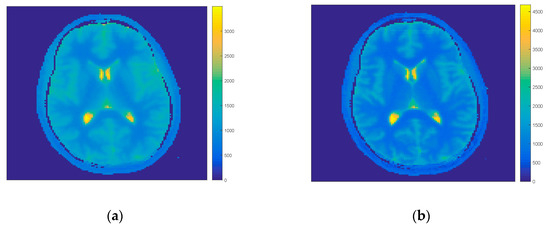

In the first step of comparison all projections were taken for the first model and iteration process. The IR-MAP and REF were taken as reference results and our approach the FIR-MAP was tested for two cases (1) with our initial model MFM and (2) with interpolated model IFM. Results of reconstruction of the FIR-MAP with both initial models and the reference IR-MAP and REF can be observed in Figure 2 for volunteer V3. The ROI analysis of regions WM, GM and CSF are presented for all methods in the form of boxplots in Figure 3. The total number of iterations in first case was set to 150 and in second case to 30. Introducing IFM improved highly results of reconstruction and it could be observed that spatial resolution was still better for the IFM initial model, which was reported [14] explaining that the reason lay in only 6 s of acquisition (minimizing motion artifacts). On the other side mean values of T1 in selected ROI and its deviation was more accurate for MFM.

Figure 2.

Exemplary results for volunteer V3 of T1 map estimation with (1) our initial model FIR-MAP-MFM (a) after termination of 150 iterations and (2) interpolated model FIR-MAP-interpolated first model (IFM; b) after termination of 30 iterations and corresponding results for reference methods REF (c) and IR-MAP (d). The FIR-MAP-MFM (a) gives similar T1 map to the REF method (c), while the higher spatial resolution can be observed for the FIR-MAP-IFM (b) and the IR-MAP (d).